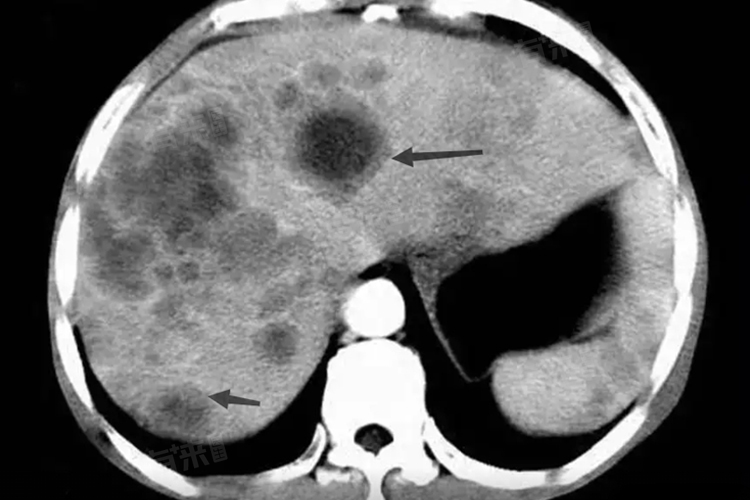

牛眼征是医学影像学术语,与转移性肝癌等肝脏病变密切相关,其病因多样,症状因个体差异而异,治疗包括药物、手术、放射、介入及化疗,治愈可能性取决于疾病性质、阶段及患者健康状况。

- 牛眼征的出现与肝脏的继发性肿瘤有关,如腺癌的肝转移;肝硬化、胆汁淤积性肝硬化、酒精性肝硬化以及血吸虫病性肝硬化等也可能导致肝脏出现类似牛眼征的影像学表现,通常是由于长期肝脏炎症、纤维化,或特定病原体感染所致,影响肝内的血液循环和组织结构,形成特定的影像学改变。

- 牛眼征本身并非一种症状,而是疾病在影像学上的表现,导致牛眼征出现的疾病,如转移性肝癌或各种类型的肝硬化,伴随着临床症状,可能包括肝区疼痛、黄疸、腹水、乏力、食欲不振、体重下降等,具体症状因个体差异和疾病进展阶段而异。